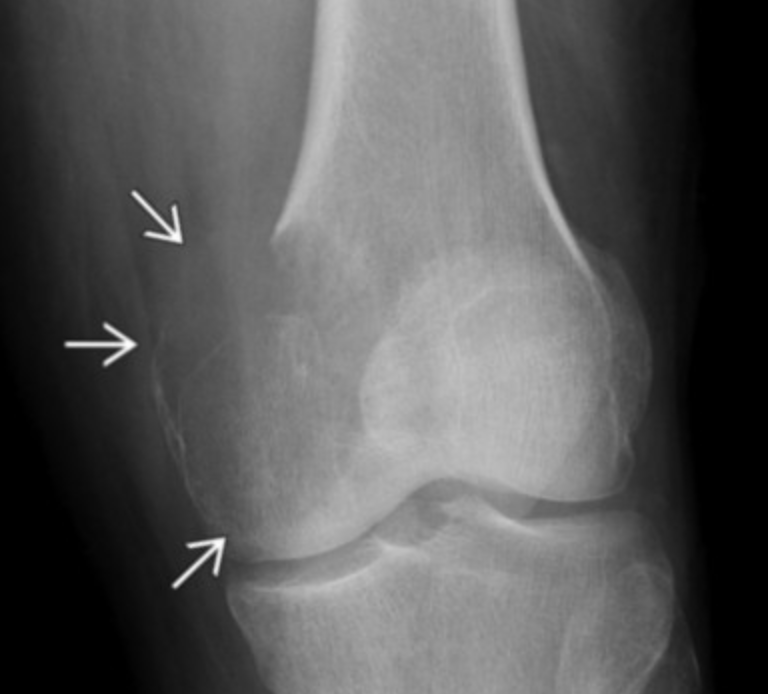

PERI-osteal Osteosarcoma

• Age 15-25 yo

• Looks more ill defined and lucent

• Diaphysis

• Medial distal femur

• Wraps circumferentially around bone

• Intermediate prognosis